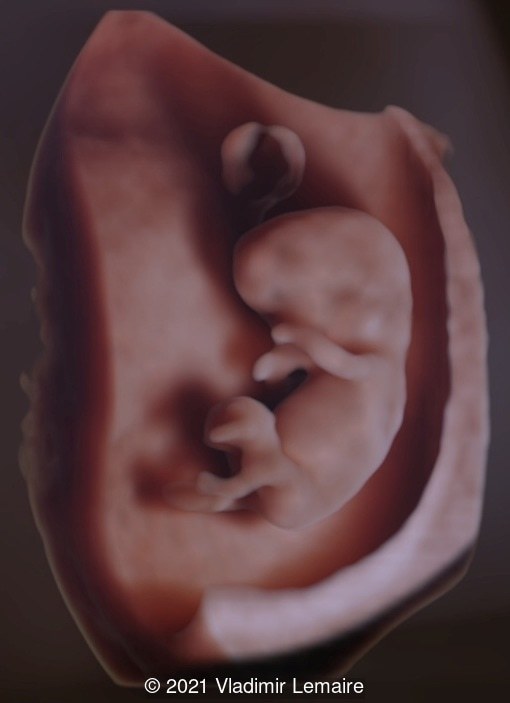

3D image of a normal embryo with a crown-rump length of 30.8 mm. Surface rendering with shadow highlights the outer surface of the embryo, umbilical cord and yolk sac.

Image 5 3D image of a normal embryo with a crown-rump length of 30.8 mm. Surface rendering with shadow highlights the outer surface of the embryo, umbilical cord and yolk sac.